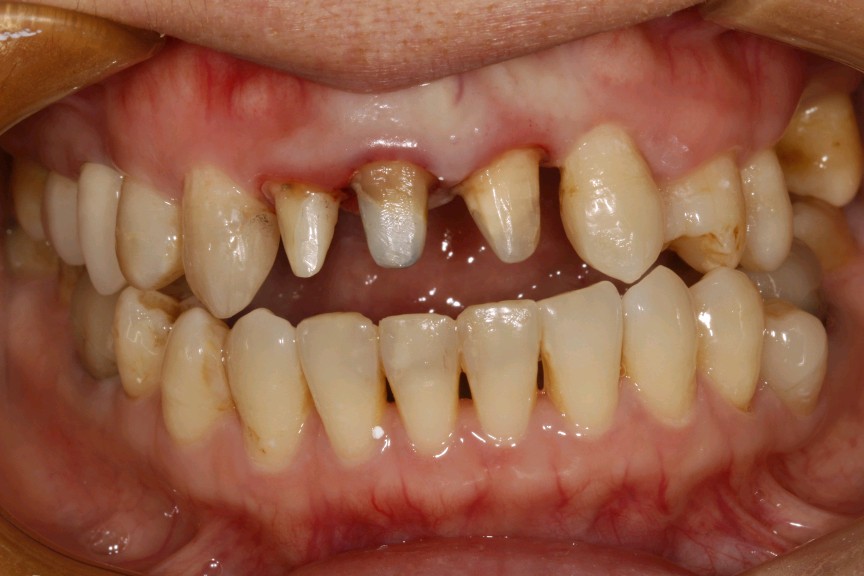

患者女,三十岁,11、12、21牙已行根管治疗,11、21烤瓷全冠修复。由于长时间烤瓷牙的佩戴,导致牙龈边缘发黑,颈缘处牙龈组织出现"黑线"。腭侧部分也出现了崩瓷的现象。对于这种情况,建议患者尽早重新修复,避免二次伤害。患者最终选择重新修复,也给出患者合理的方案,患者选全瓷冠修复,与今日佩戴完毕。边缘密合度良好,形态色泽自然美观,患者满意。

术后